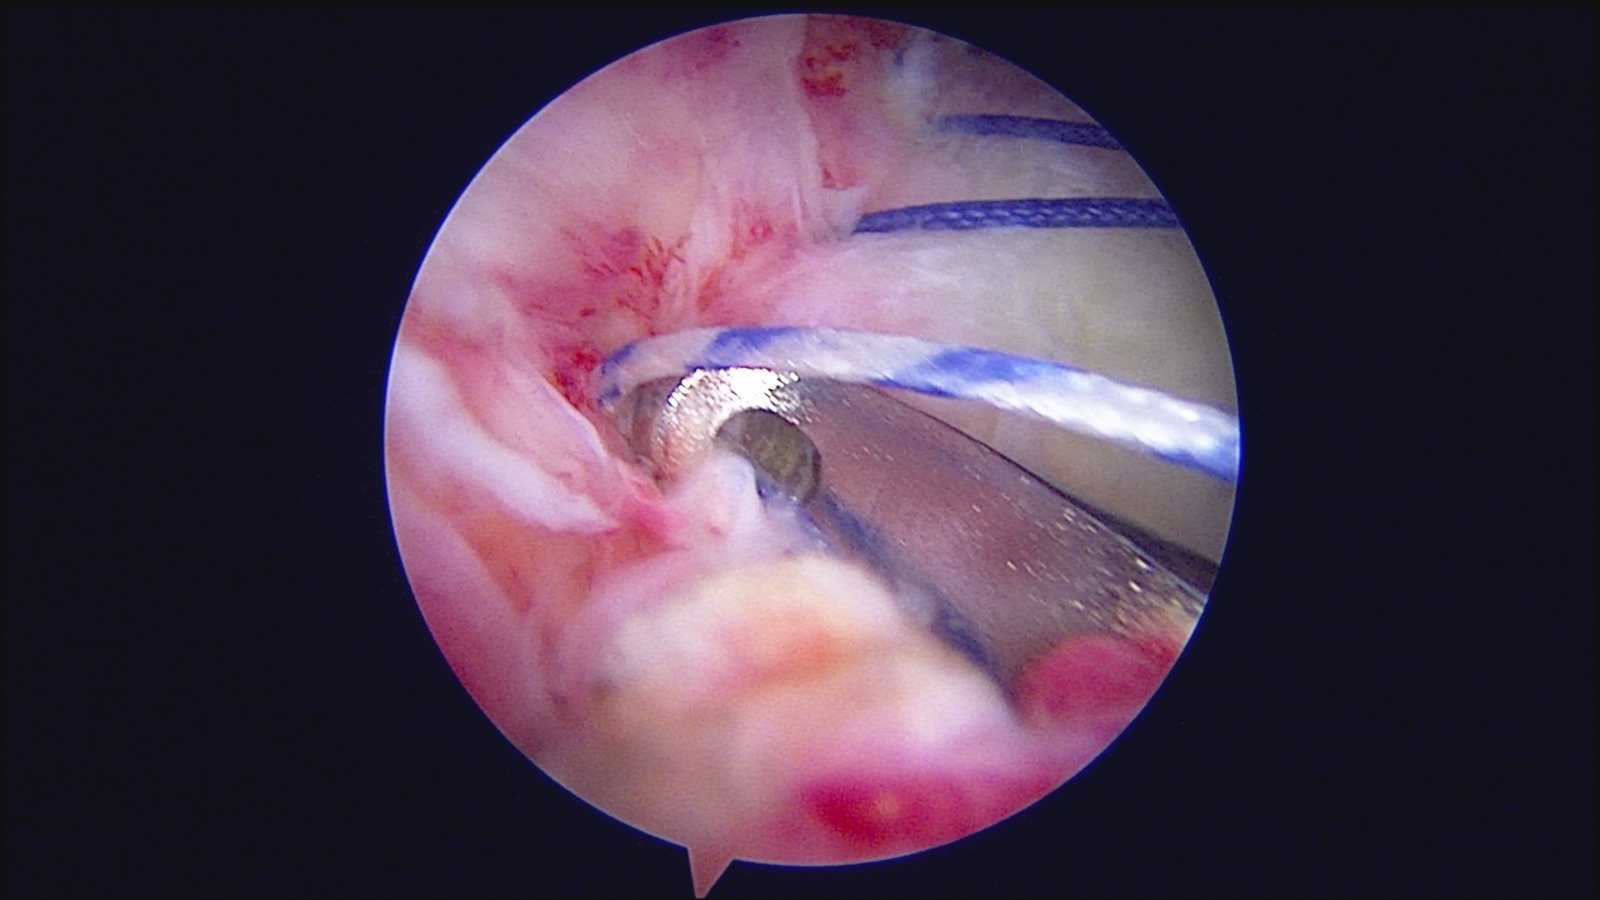

GalleryShoulder rotator cuff repair Meniscus root repair Meniscus repair Bankart repair for recurrent shoulder dislocation ACL reconstruction Machines Instruments